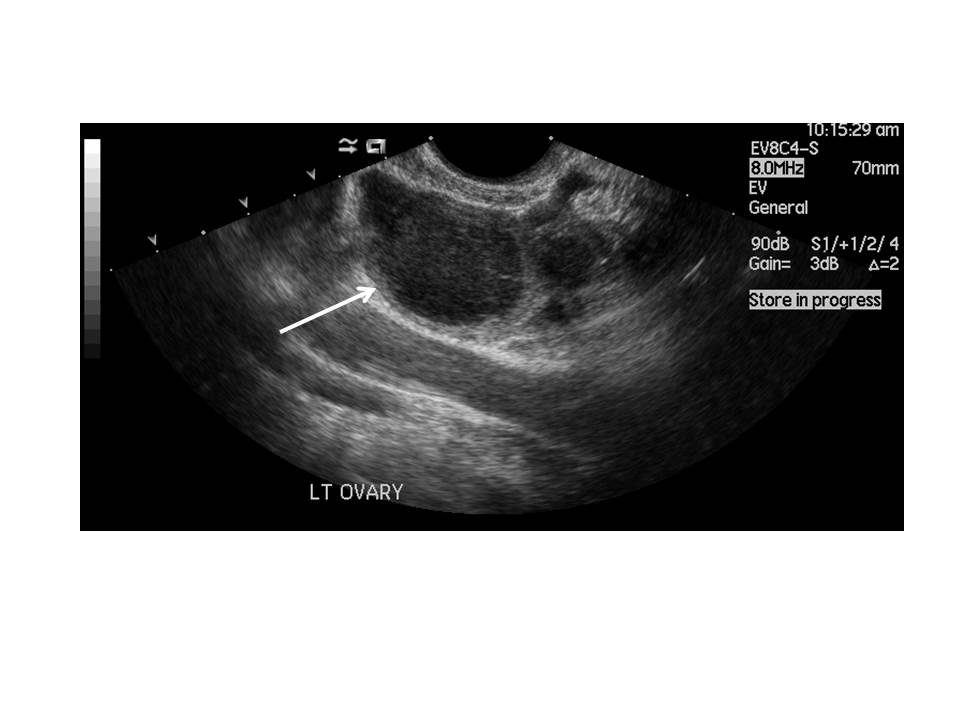

A 37 year-old lady with a three month history of pain in the right upper quadrant was referred by her GP for an abdominal ultrasound. She also had a long history of pelvic pain.

Ultrasound images are shown in Figs 1, 2 and 3.